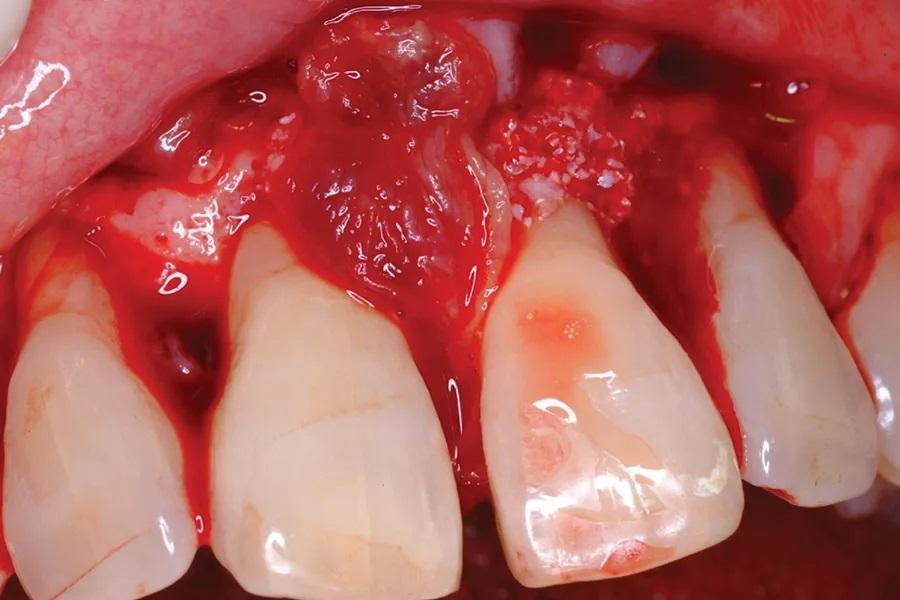

Фото 3. Интраоперационное клиническое изображение, показывающее пародонтальный дефект.

65-летняя некурящая пациентка с пародонтитом обратилась с костным дефектом на мезиальной поверхности верхнего левого центрального резца (зуб № 2.1) (Фото 1 и Фото 2). Зарегистрированный индекс подвижности (по Грейсу и Смейлсу) составил 2 степень, т.е. движение в вестибуло-лингвальном направлении на 1–2 мм. Во время процедуры пластики был отслоен слизисто-надкостничный лоскут, обнажен глубокий пародонтальный дефект (Фото 3 и Фото 4). Аутогенная кость была взята из ветви нижней челюсти и смешана в соотношении 1:2 с ДМБК (покрытый ОКФ, 100% губчатая кость) (Ti-oss, Chiyewon Co. Ltd.; распространяется как creos xenoform, Nobel Biocare). Полученный материал был смешан с высококонцентрированными тромбоцитами, полученными путем дополнительного центрифугирования БоТП (упоминается как концентраты тромбоцитов в протоколе, адаптированном автором), к которым были добавлены тромбин и кальций для образования коагулированной массы (Фото 5), использованной для заполнения дефекта (Фото 6). Показано, что тромбин и кальций in vitro и in vivo активируют тромбоциты для высвобождения факторов роста, тем самым стимулируя остеобласты, усиливая ангиогенез и способствуя миграции клеток.